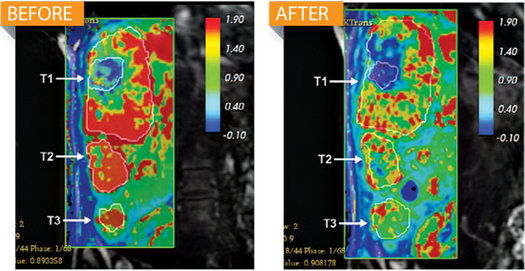

核磁共振掃描顯示,使用ALN-VSP療法后,肝臟腫瘤中的血流量(紅色)明顯減少。

到今年6月,阿爾尼拉姆公司稱,通過“喚醒”人體自身的一種很少使用的免疫防御系統(tǒng),ALN-VSP成功切斷肝癌患者體內(nèi)腫瘤62%的血流量。在治療肝癌時,傳統(tǒng)藥物一般使用消除致病蛋白質(zhì)的方法,而ALN-VSP則通過核糖核酸干擾(RNAi)療法直接阻止細(xì)胞生成致病蛋白質(zhì)。